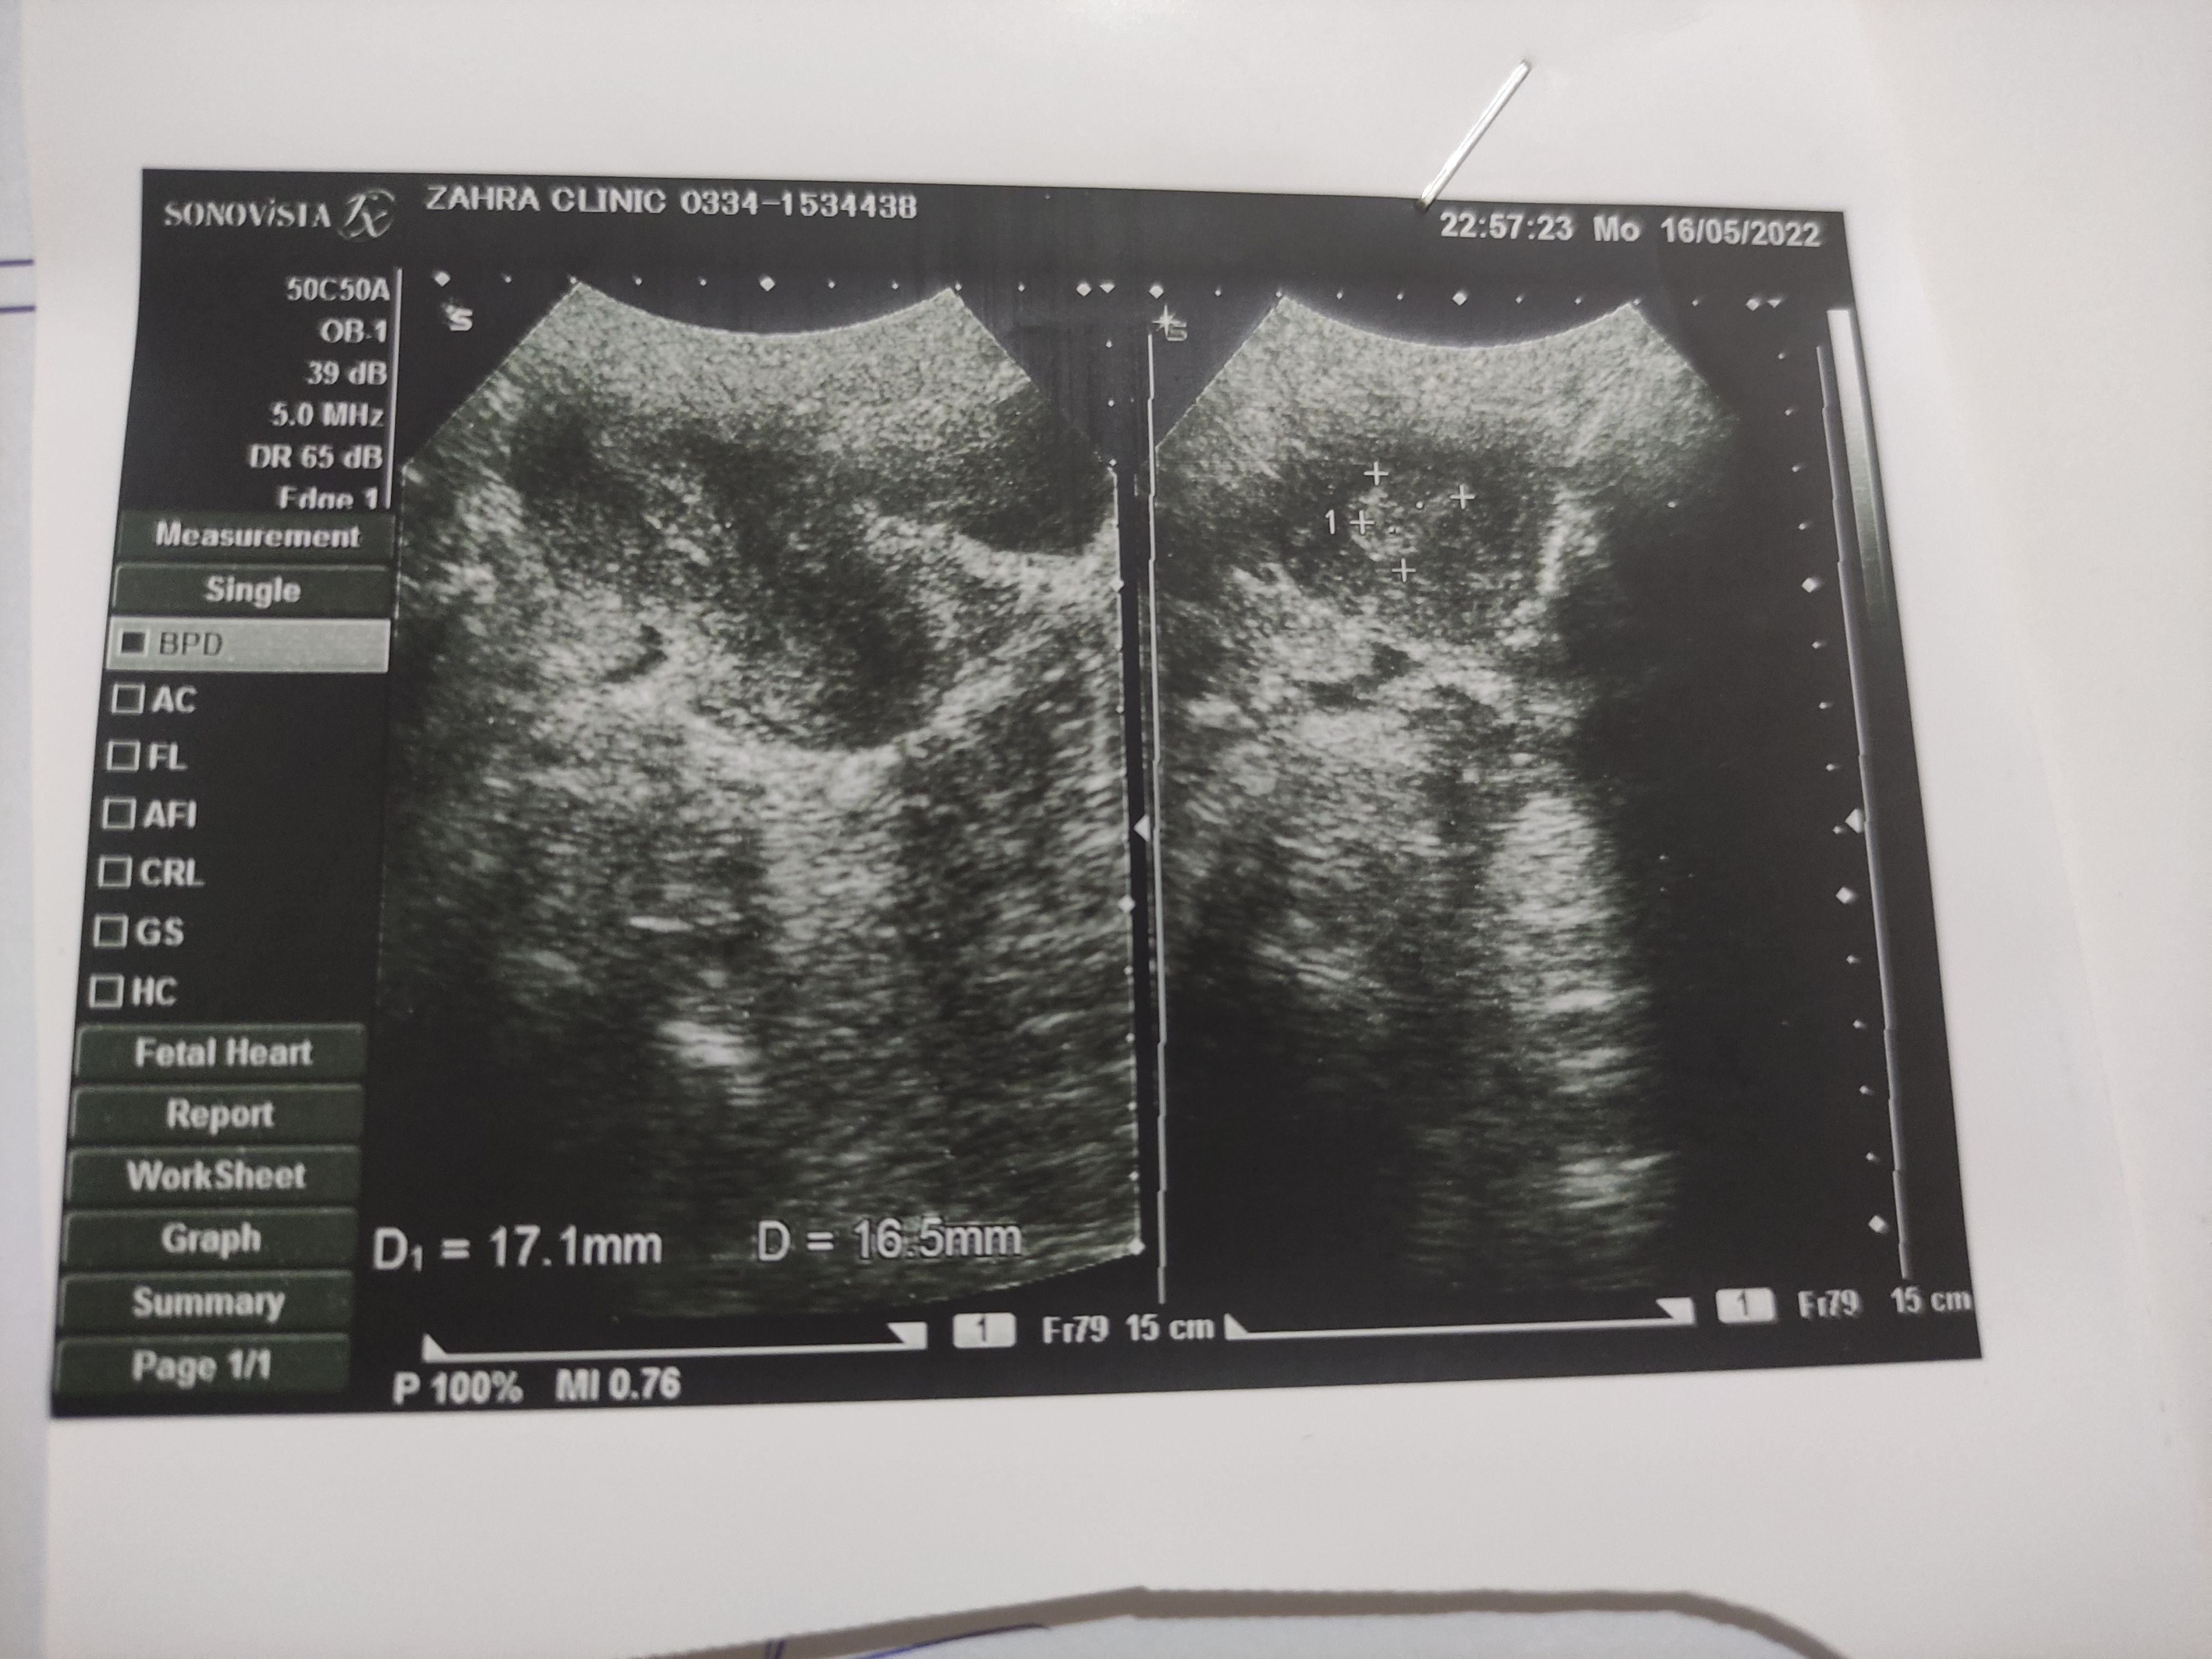

i was 15 days late from my periods than i had periods, heavy bleeding before periods i did a pregnancy test and it was positive, after 10 days of periods i am still testing positive, 2 days before i had an ultrasound a doctor said there is no pregnancy only a blood clot which will eventually come out. now i dont understand why i am testing positive. my last periods were on 28 march and i had period on 13. it was clotted blood and just like normal periods bleeding.

2 wks tk test positive ata h And apkA missed abortion h apka test positive aey ga kionky piece of conception under h cavity mb

pregnancy test remains positive six weeks after you hvhd miscarriage...but in your case I advise you to do serum bhcg levels and repeat after forty eight hours to confirm the fetal viability...also take second opinion frm sum good gynaecologist